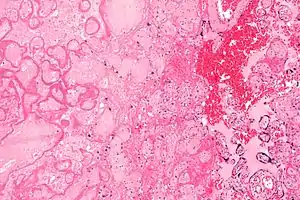

| Micrograph of a placental infarct (left of image), a cause of intrauterine hypoxia. H&E stain. | |